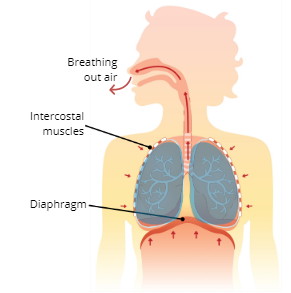

What are the 3 major respiratory muscles?

Diaphragm, External Intercostal Muscles, and Internal Intercostal Muscles

Diaphragm

a dome-shaped muscle below the lungs that separate the thoracic and abdominal cavity

Internal Intercostal Muscles

pull ribs downwards and inwards

Exhalation (Expiration)

Explain the Process of Exhalation (Expiration

The intercostal muscles and diaphragm relax, which causes the thoracic cavity to reduce in size which decreases lung volume, this then creates pressure that pushes air out of the lungs